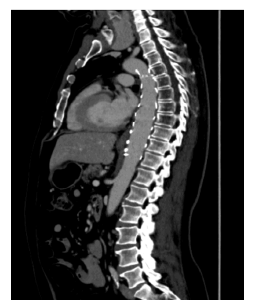

No adverse events occurred during the postoperative period. The patient was discharged on a regimen of aspirin 100 mg and rivaroxaban 20 mg and has continued under close follow-up in outpatient care for five years, remaining asymptomatic. Follow-up CTA confirmed the correct positioning of the thoracic aortic graft and showed no evidence of thrombus recurrence, Figure 3.

A thoracic stent graft is visible, adequately excluding the pre-existing mural thrombus